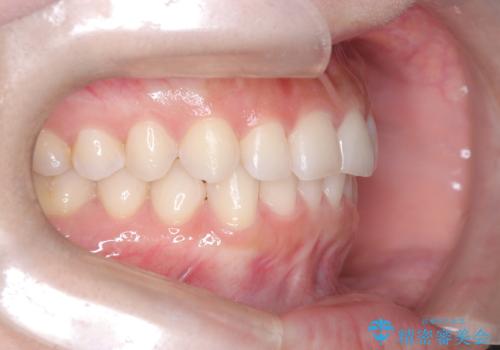

- 前歯のガタガタが気になるとのことでご相談いただきました。診察すると、歯列のスペースが不足し、前歯が重なっている状態でした。抜歯をせずに整えるため、歯と歯の間をわずかに削るIPR(歯列幅径削除)と、奥歯を後方へ動かす遠心移動を組み合わせてスペースを確保しながら並べる治療計画を立てました。

インビザラインを用いて歯を少しずつ移動させながら、IPRで微調整を行い、スペースを確保しました。また、奥歯を遠心移動させることで、前歯を自然な位置に並べることができました。治療後は、「ガタガタがなくなり、スムーズな歯並びになった」と患者様にもご満足いただきました。